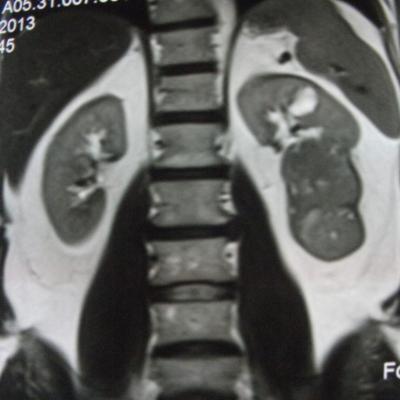

такое заключение: Левая почка: расположена обычно, увеличена, общими размерами около 13х5,5см. В области средней и нижней трети почки определяется объёмное образование неправильной формы, деформирующее наружный контур почки, распространяющиеся с чашечно-лоханочную систему. Опухоль имеет четкие неровные бугристые контуры с наличием псевдокапсулы, неоднородной структуры с признаками распада, максимальными размерами около 78,7х47х48мм